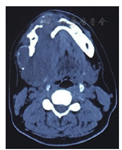

Ⅱ度松动,无叩痛。下颌骨CT影像示下颌骨髁突、右侧下颌体及下颌支见不规则膨胀性骨质破坏,骨皮质变薄、硬化,局部骨皮质不连,大小约9.6 cm×5.5 cm×8.0 cm,肿物边界清,内部密度均匀,CT值为35 Hu,增强扫描未见明显强化,右侧颞下颌关节解剖结构正常,双侧颈部未见明显增大淋巴结影像(图1)。头颈部CT血管造影检查显示:双侧椎动脉及双侧颈总动脉粗细均匀,未见明显管腔狭窄或瘤样扩展,颈部血管走形自然,呈均匀一致强化,未见明显异常。CT诊断:下颌骨良性肿瘤,成釉细胞瘤可能性大。临床诊断:右下颌骨成釉细胞瘤。治疗:全麻下行下颌骨右侧肿物切除术+下颌骨右侧切除术+下颌骨左侧部分切除术+下颌骨双侧缺损左腓骨瓣血管化游离移植修复术+双侧骨内坚固内固定术+小动脉吻合术+临近瓣转移修复术+气管切开术。术中见下颌骨右侧肿物突破下颌骨皮质,下颌体右侧向下颌下区膨隆。